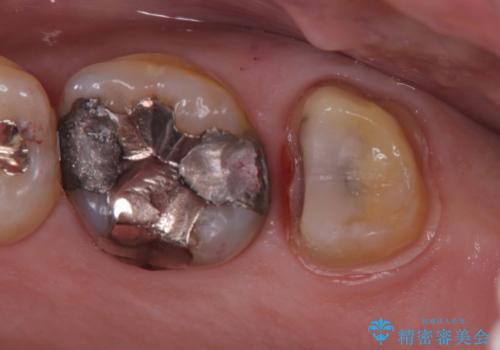

今回も不適合な銀歯を外したらその下は虫歯になっていました。

虫歯を除去後、フルジルコニアクラウンで治療を行いました。

不適合な銀歯を外して、虫歯の除去後にシリコンで印象をとりフルジルコニアクラウンで治療を行いました。